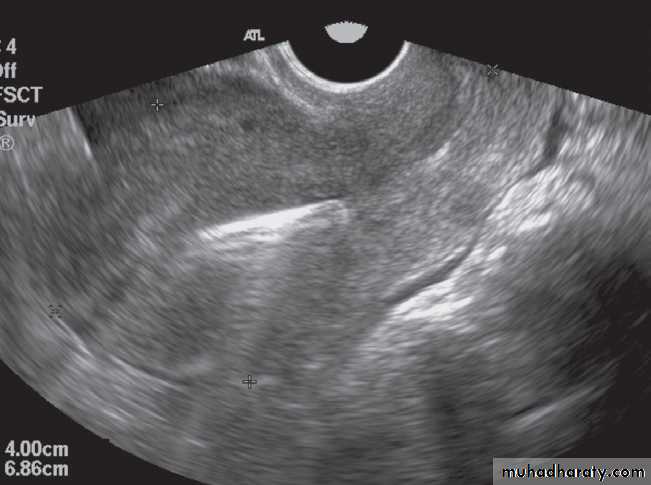

Detection of intrauterine contraceptive devices

The lost intrauterine contraceptive device (IUCD) is a relatively common problem and ultrasound should be the first investigation. Different devices have characteristic appearances. They are seen as highly reflective structures and their relationship to the uterine cavity can be determined.Hysterosalpingography is a contast study of uterus & both fallopian tube used to investigate selected cases ofinfertility in order to assess the patency of the fallopian tubes. A catheter with a seal to prevent leakage from the external cervical os is inserted into the uterus. Sufficient iodinated contrast is then injected under fluoroscopic control to fill the uterus and fallopian tubes .